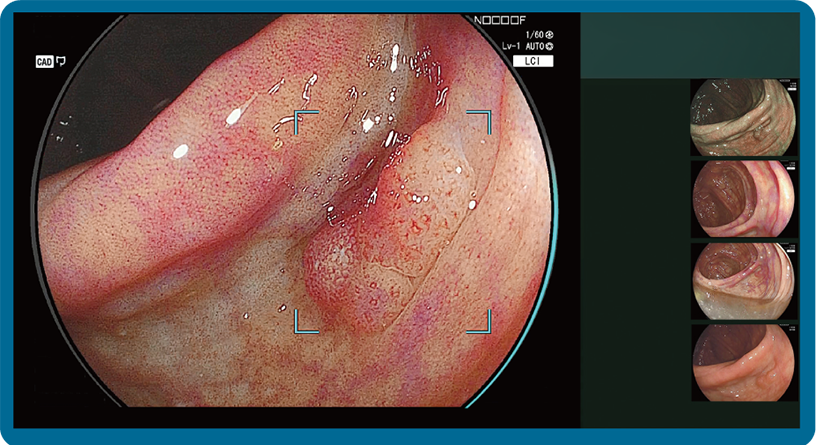

CAD EYE is FUJIFILM's brand name of computer-aided diagnosis (CAD) function for endoscopy. CAD EYE has been developed utilizing AI deep learning technology with an immense amount of clinical images.

Detection